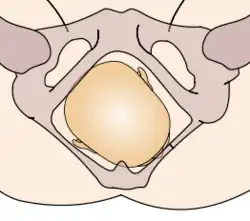

The vertex presentations are further classified according to the position of the occiput, both right, left, or transverse and anterior or posterior:

- Left Occipito-Anterior (LOA), Left Occipito-Posterior (LOP), Left Occipito-Transverse (LOT)

- Right Occipito-Anterior (ROA), Right Occipito-Posterior (ROP), Right Occipito-Transverse (ROT)

The occipito-anterior position is ideal for birth; it means that the baby is lined up so as to fit through the pelvis as easily as possible. The baby is head down, facing the spine, with their back anterior. In this position, the baby's chin is tucked onto their chest, so that the smallest part of their head will be applied to the cervix first. The position is usually "Left Occiput Anterior", or LOA. Occasionally, the baby may be "Right Occiput Anterior", or ROA.[5]